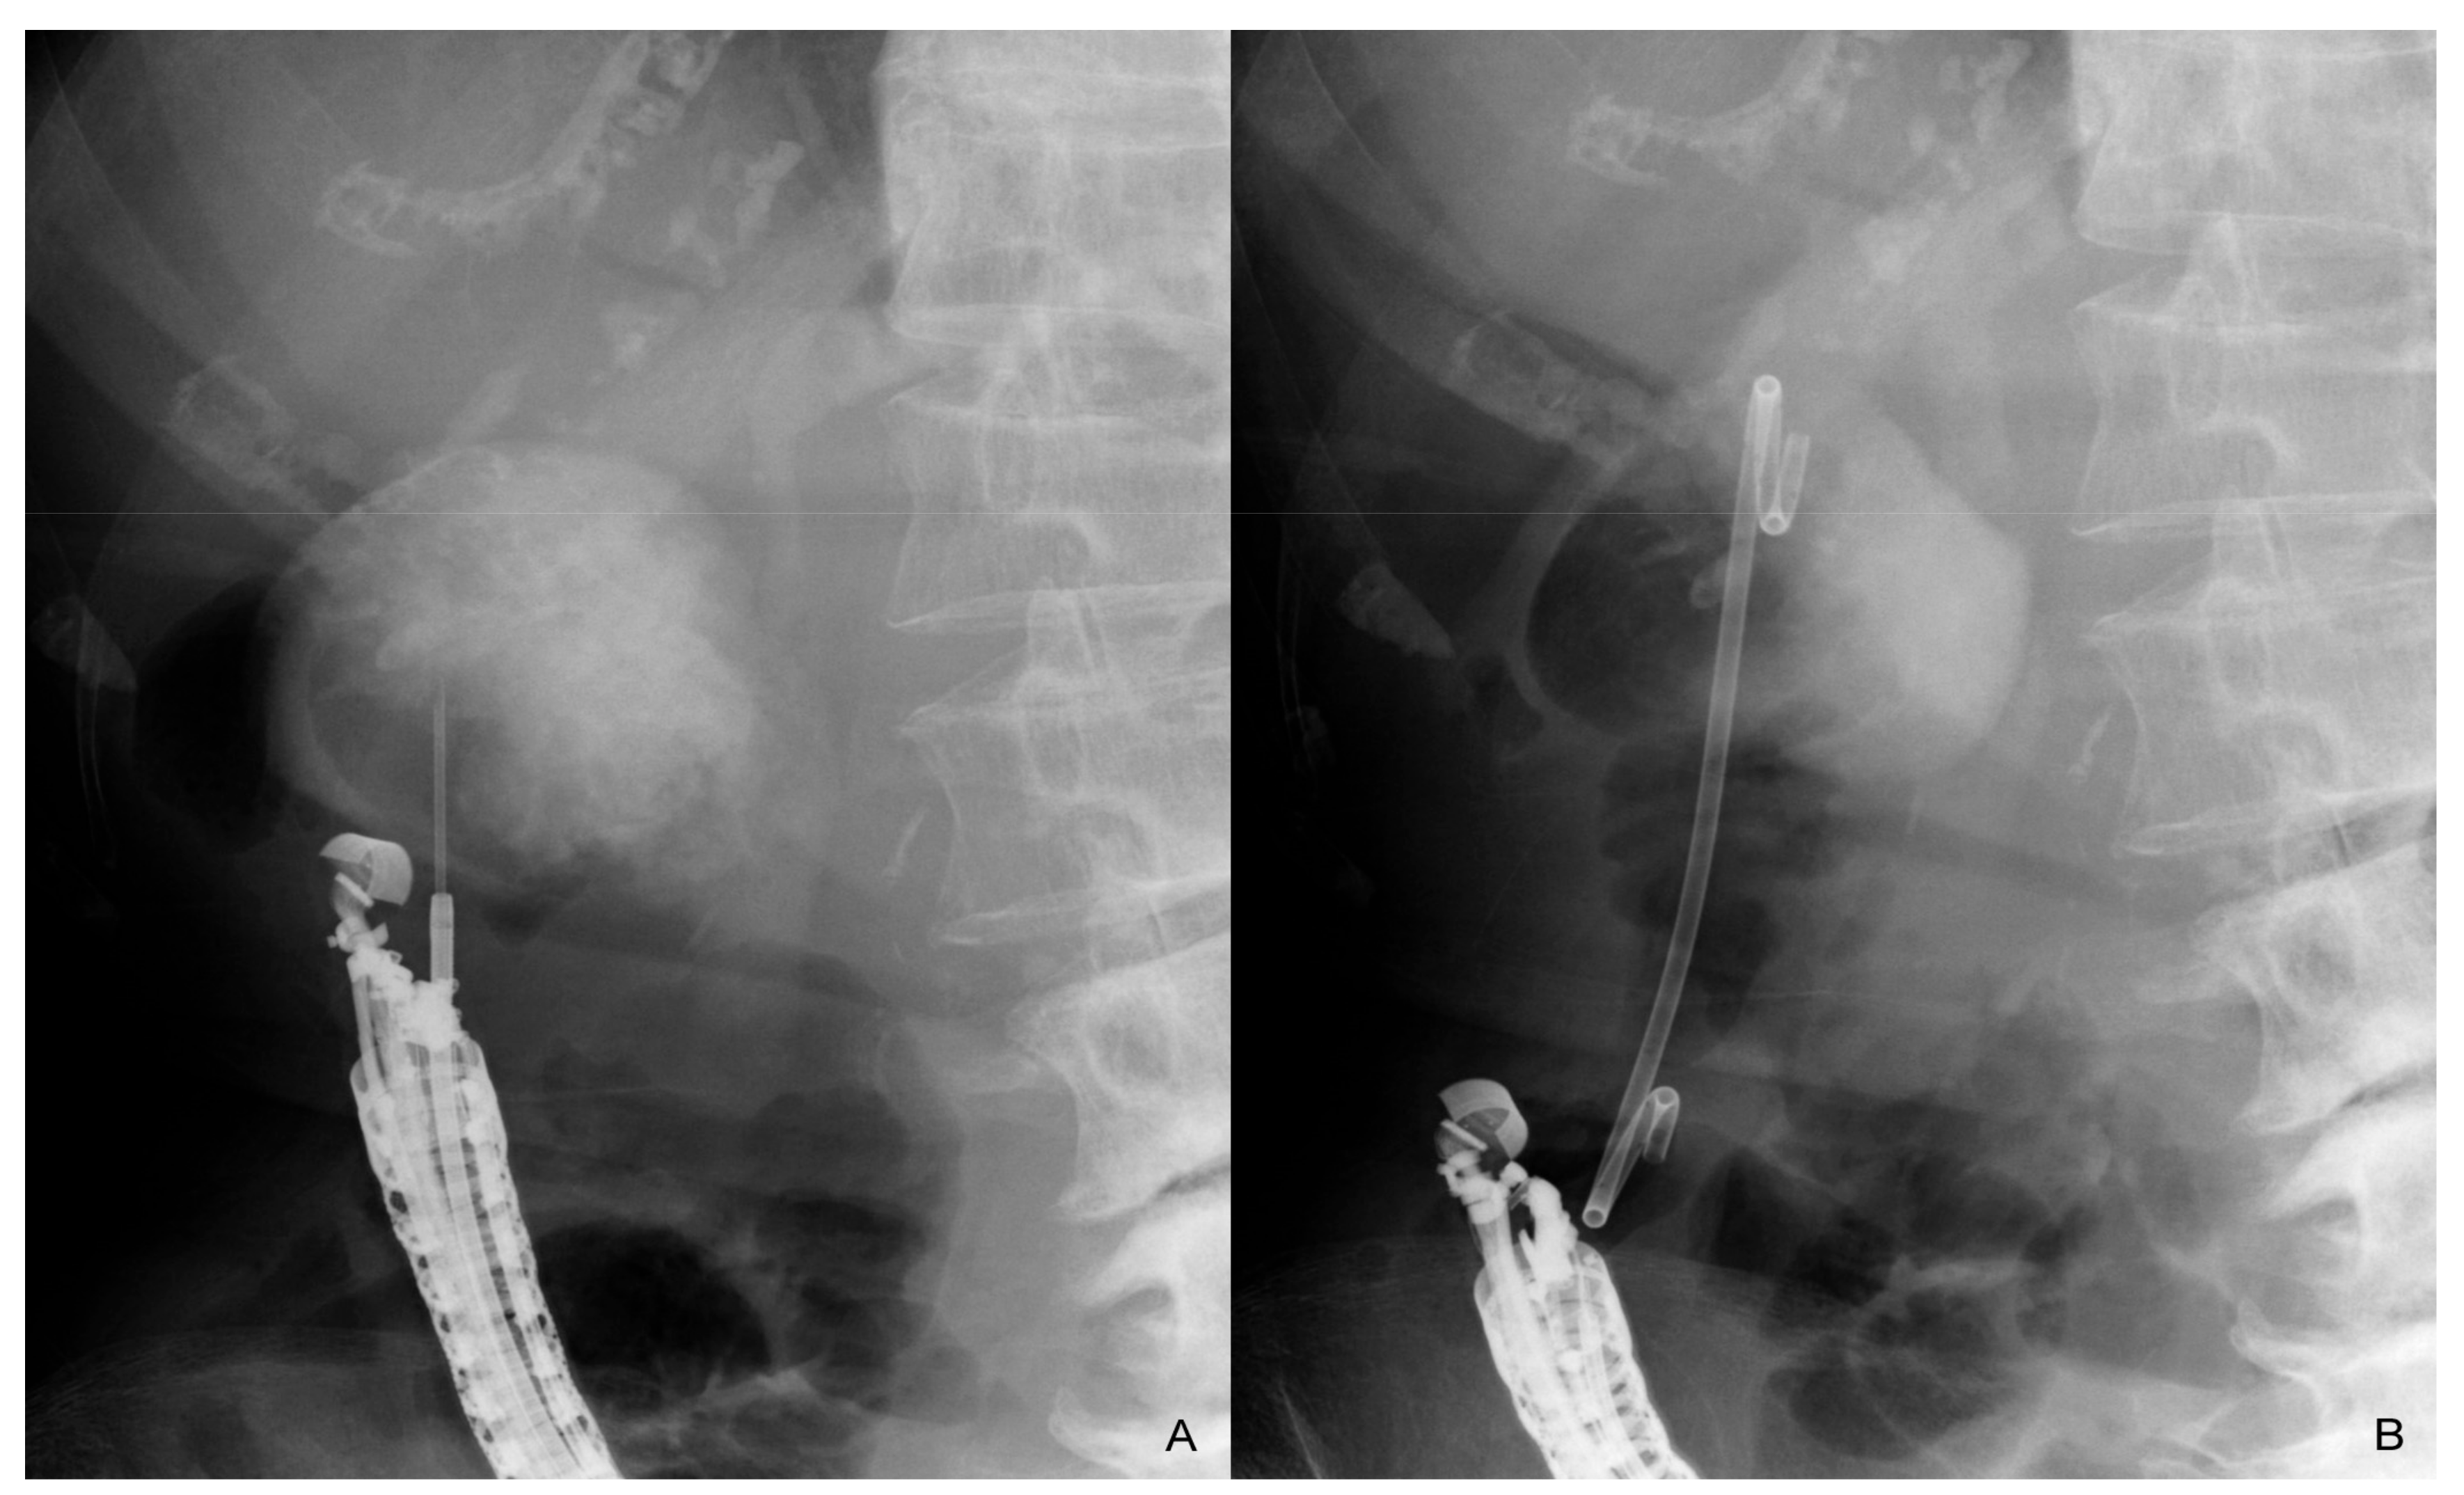

Figure 2.

Endoscopic ultrasound-guided gallbladder drainage. After the gallbladder is punctured transduodenally (A), a guidewire is placed in the gallbladder. A 7 Fr double-pigtail plastic stent is placed after dilation of the fistula (B). The stent remains in place after the procedure without any stent exchange and removal.